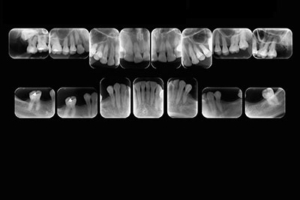

Radiografía Periapical Total

La radiografía periapical forma parte de las radiografías intraorales. Su objetivo principal es ver los ápices dentales, la punta de las raíces, la corona, el tejido óseo y alrededor de los dientes.